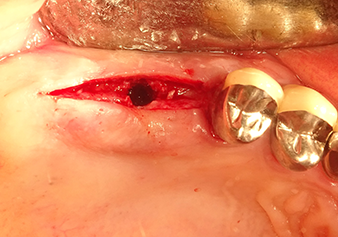

La membrane de Schneider est étirée sur 1,5-2 mm au-dessus de l’abord osseux.

Fig.4 : Contrôle intermédiaire : La hauteur osseuse au-dessus du plancher du sinus maxillaire est d’environ 4 mm dans la zone palatine et buccale. La membrane de Schneider est étirée sur 1,5-2 mm au-dessus de l’abord osseux.